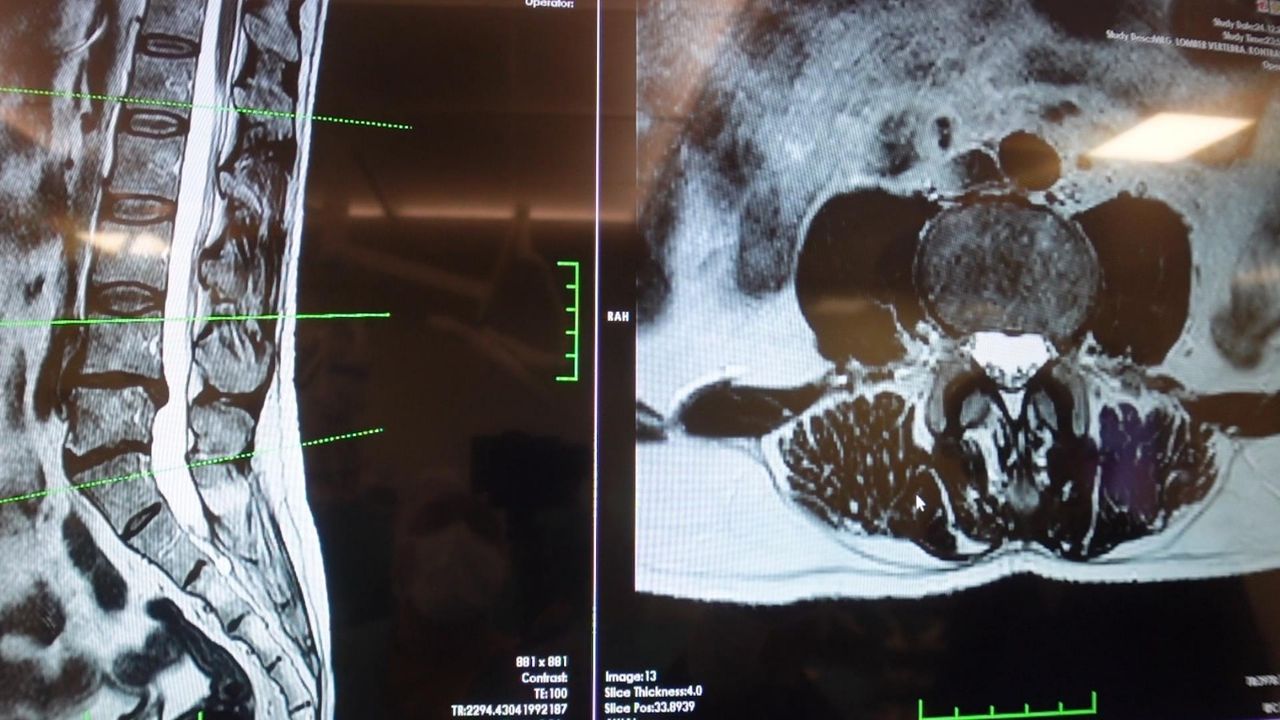

Prof. Dr. Erol, bir diğer önemli hasta grubunun ise omurilik kanal darlığı yaşayan hastalar olduğunu söyledi.

Dejeneratif süreçler sonucu omurilik kanalında ve sinir köklerinin geçtiği kemik kanallarda daralma ve kireçlenme oluştuğunu belirten Erol, bunun sinirlerde sıkışmaya neden olduğunu ifade etti.

Bu hastalarda özellikle ayakta dururken ya da yürürken bel, kalça ve bacaklara yayılan ağrılar görüldüğünü aktaran Erol, yürüyüş mesafesi arttıkça hastaların oturma ve dinlenme ihtiyacı hissettiğini söyledi.